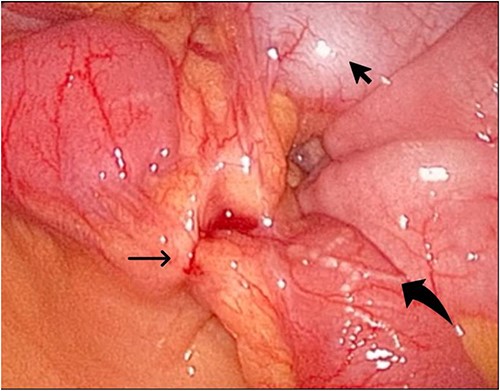

During her hospital stay, the patient showed no improvement regarding abdominal pain, nausea, or abdominal exam. Therefore, she was offered a laparoscopic exploration to verify the diagnosis of a FB to which she agreed. She was taken to the operating room, and the exploration showed an inflammatory process in the LLQ (Fig. 3) with the sigmoid colon attached to the area of the inflammatory reaction. A FB was found in the mesentery of two loops of the ileum 100 cm from the ileocecal junction (Figs 4 and 5). Removal of the FB safely and milking of the small bowel showed no leakage of bowel contents (Fig. 6). And, exploring the rest of the abdomen showed no other pathology and normal ovaries (Figs 7 and 8); the procedure was uneventful. The FB was identified as a toothpick, 3 cm in length (Fig. 9).

The laparoscopic exploration showed a FB in the mesentery of two loops of the ileum 100 cm from the ileocecal junction—upon partial exposure of the site of the toothpick.